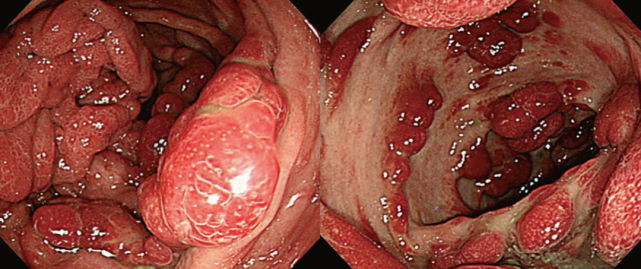

病例结肠多发性息肉分次切除内镜下分片黏膜切除术切除巨大息肉一枚